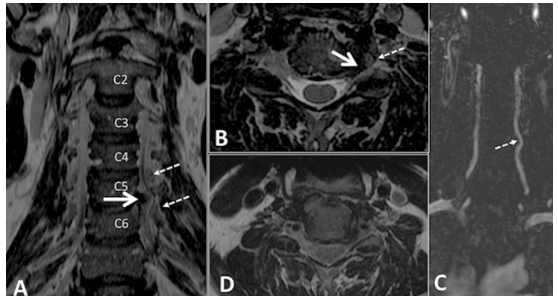

Descubra a inovação que permite à Ressonância Magnética detalhar o osso com precisão de Tomografia Computadorizada.